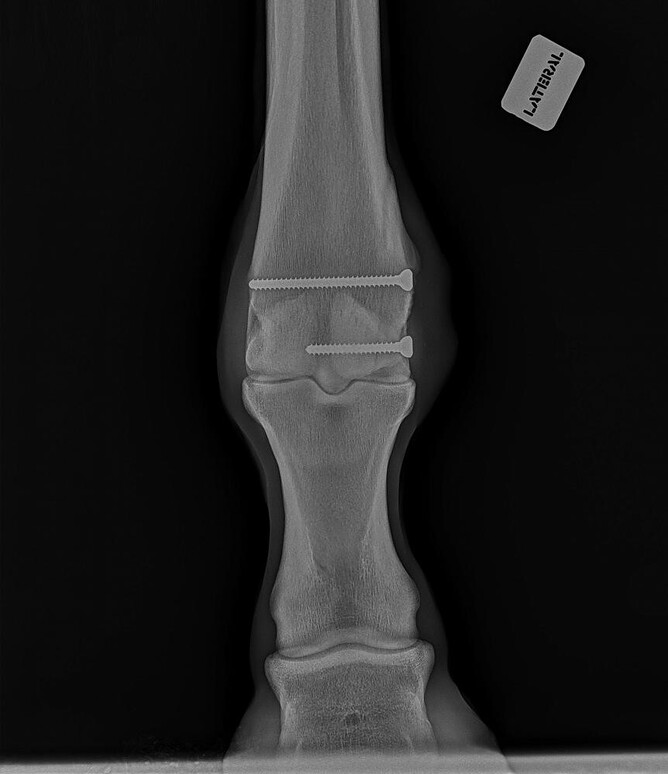

The repair of the fracture shown in Figure 2 was performed on a standing horse. The finished repair is in Figure 3. Figure 4 shows standing screw placement into a knee fracture.